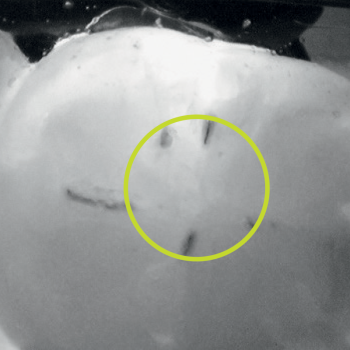

Occlusal caries

Secondary caries

Cracks